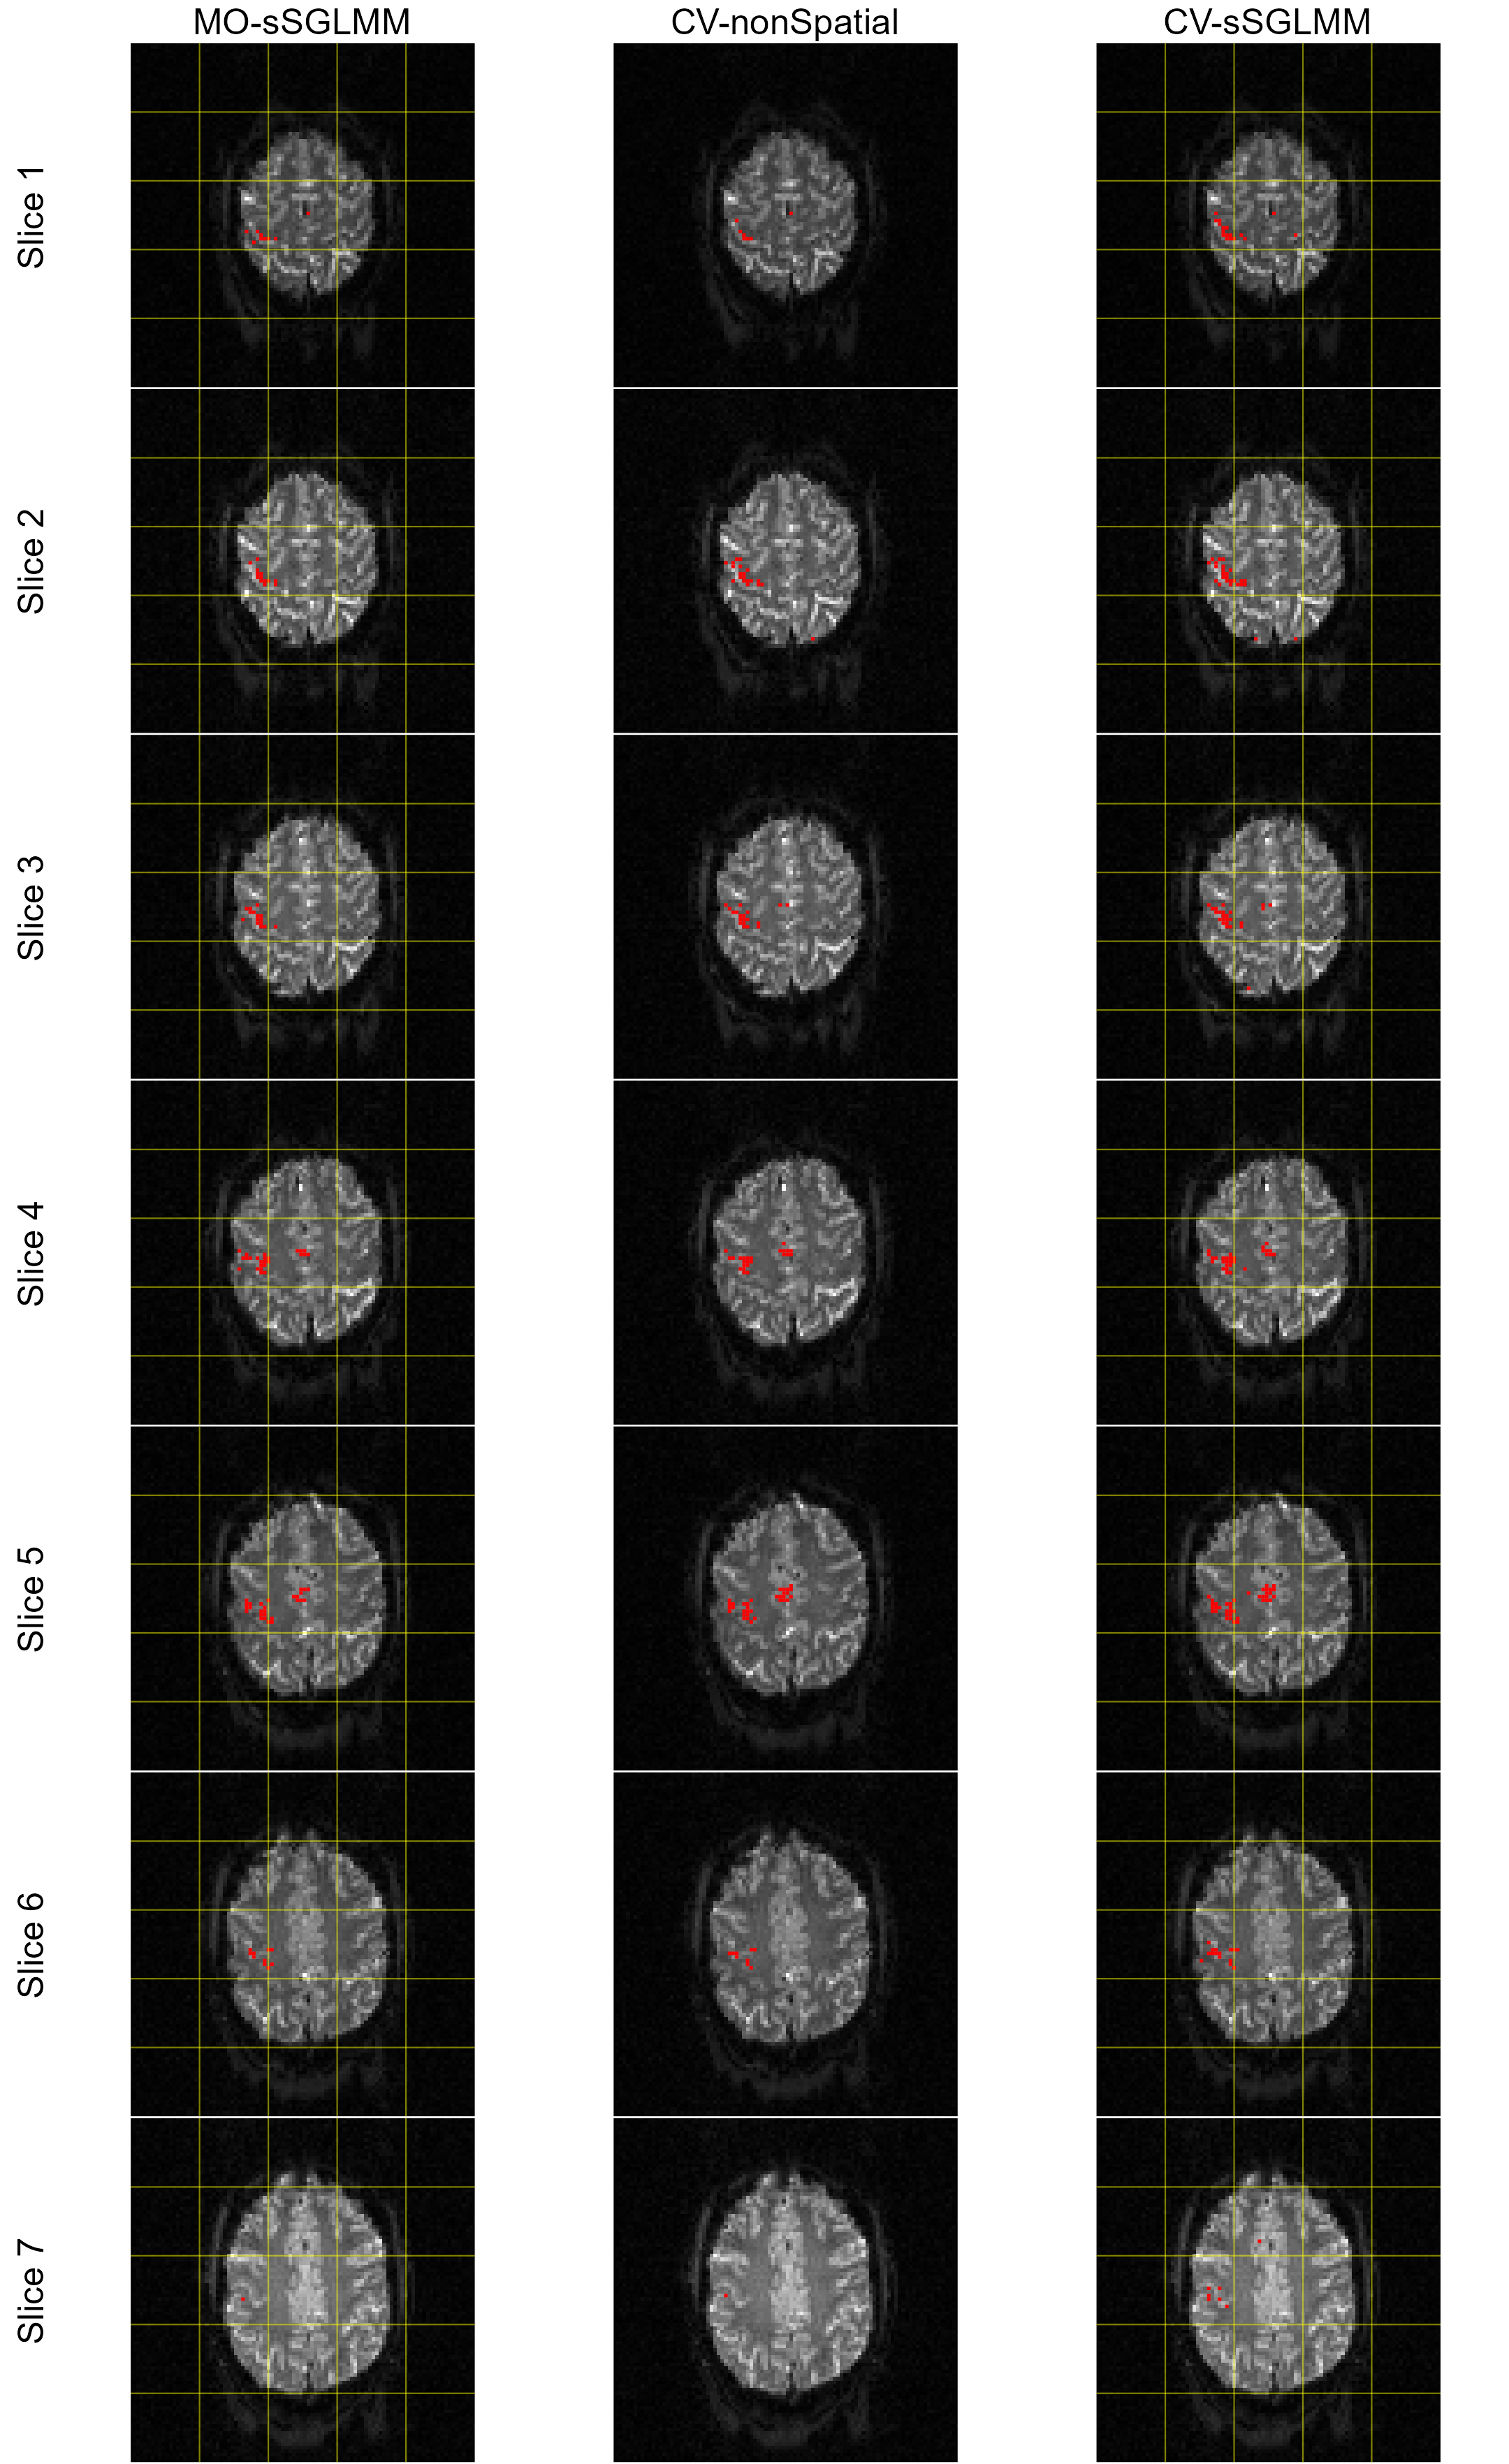

Activation then decreases from slice 4 to slices 3 and 5 and is weakest in slices 2 and 6. Slices 1 and 7 exhibit no activation. It’s important to note that, with dynamic phase, the model from Lee et al. (2007) is not equivalent to that from Rowe (2005b) as indicated in Rowe (2009). This discrepancy suggests the proposed model is under model misspecification in this scenario. However, as both βRevsuperscriptsubscript𝛽𝑅𝑒𝑣\beta_{Re}^{v} and βImvsuperscriptsubscript𝛽𝐼𝑚𝑣\beta_{Im}^{v} in model (2) include magnitude and phase information, and given that prior studies (Yu et al., 2018, 2023) have used the Lee et al. (2007)-based model to process this dataset, we deem it worthwhile to test our model on these data. We set G=49𝐺49G=49 and a threshold of 0.8722 for both MO-sSGLMM and CV-sSGLMM, with ψ𝜓\psi set to Φ1(0.50)superscriptΦ10.50\Phi^{-1}(0.50) and Φ1(0.11)superscriptΦ10.11\Phi^{-1}(0.11), respectively. For CV-nonSpatial, the threshold is set to 0.5, again following the advice of Yu et al. (2018). Activation maps are presented in Figure 6. We indeed observe that our model tends to overestimate the magnitude. Since the magnitudes are overestimated, we scale the estimated magnitude to the range of true magnitude in the corresponding slice. True and (scaled) estimated magnitude maps are displayed in Figure 7.

Further numerical results, displayed in Table 4, show a pattern of the CV-sSGLMM model outperforming both the MO-sSGLMM and CV-nonSpatial models across different slices in terms of detecting true positives (TP). It should be noted, however, that the MO-sSGLMM model achieves a 100% precision (no false positives, FP) for most slices, albeit at the cost of a low recall rate (high false negatives, FN), indicating that the model is more conservative in identifying activated voxels. For the CV-nonSpatial model, although it exhibits good precision across the slices, the recall rates remain lower, specifically in the slices with weaker activation strengths (slices 2 and 6). This performance pattern suggests that the model struggles to detect activations in areas with low CNR, highlighting a limitation when dealing with real-world fMRI datasets that often feature low CNR. In comparison, the CV-sSGLMM model consistently detects a higher number of true positives across all slices, demonstrating a stronger detection power even in slices with weak activations (slices 2 and 6). This underscores the benefit of incorporating spatial information, which enhances the model’s capacity to detect weaker activations in the presence of complex noise conditions. The model also maintains a 100% precision across all slices, suggesting that the inclusion of spatial information does not lead to an increase in false positives. As anticipated, both the MO-sSGLMM and CV-sSGLMM models, which employ brain parcellation, demonstrate superior computational efficiency, even when the parallel computation is gated by a 16-core CPU. This advantage becomes even more pronounced when handling larger datasets.

Refer to caption

Figure 6: True and estimated activation maps for a realistic simulation as produced by the MO-sSGLMM, CV-nonSpatial, and CV-sSGLMM models